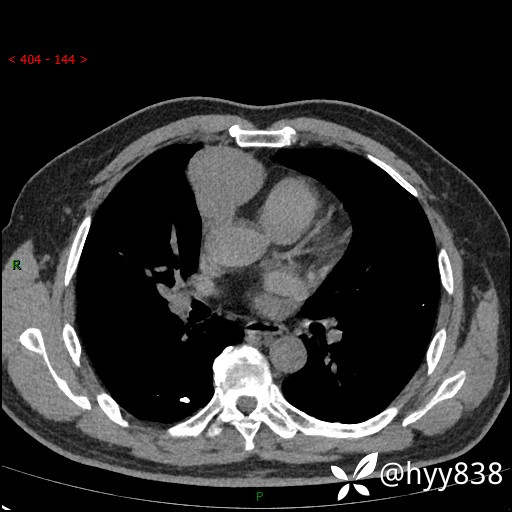

胸部CT平扫